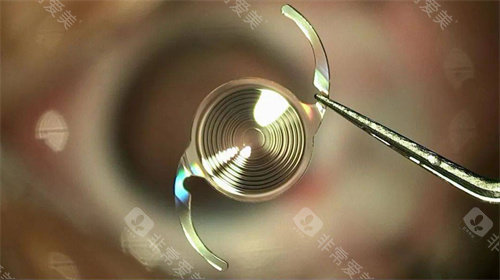

例如,美国爱尔康的PanOptix三焦点晶体,可同时满足远、中、近视力需求,适合需要频繁切换用眼场景的患者;瑞士ICL的胶原共聚物晶体,厚度仅50微米,植入后无异物感,尤其适合角膜偏薄的高度近视人群。

此外,进口晶体还提供“可调节型”“景深延长型”等创新设计,为复杂病例提供更多选择。